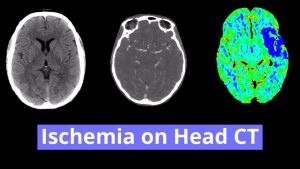

- Areas of low attenuation in the left frontoparietal white matter

- Watershed territory infarct

Areas of low attenuation in the left frontoparietal white matter in a distribution most suggestive of ACA/MCA watershed territory ischemia. No significant associated mass effect or evidence of hemorrhagic transformation.